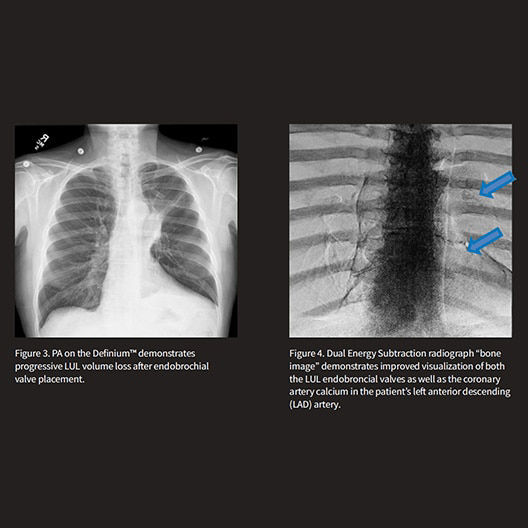

Dual Energy Subtraction

Helps eliminate obstructions from overlying bones while providing additional information.